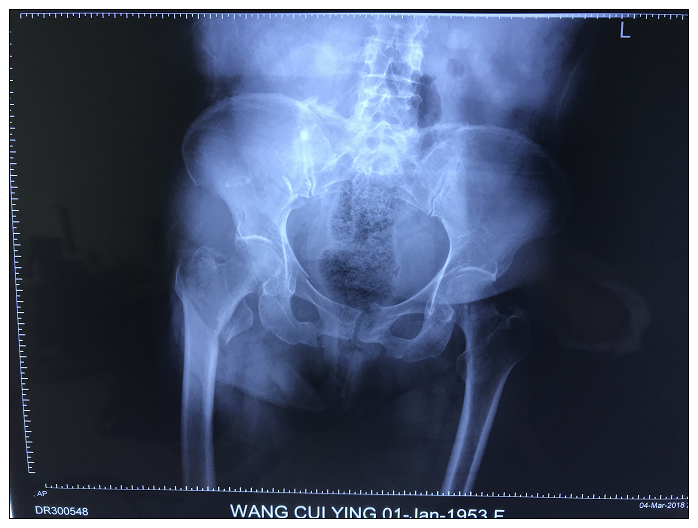

患者王某某,女,65岁。于3月4日20时发生车祸,当即右髋部剧烈疼痛伴活动受限,急诊送至我院,摄片提示骨盆骨折、右股骨粗隆间骨折,考虑骨盆骨折出血量较大且合并右股骨粗隆间骨折,为防止病情恶化及出现骨盆骨折所致的盆腔脏器损伤及失血性休克,显微骨科值班医生当即采取骨盆兜外固定及联系输血科备血,进一步了解患者基本情况得知患者既往有高血压、心脏病、糖尿病等基础疾病。针对患者基础疾病较多,手术风险较大,床位医生积极完善相关检查及相关科室会诊,经显微骨科全体医师讨论决定采用微创技术处理骨盆骨折,减少术中创伤及缩短手术时间来降低手术风险。患者于3月14日顺利完成手术,目前患者术后恢复良好。该患者的成功救治体现了微创技术在处理基础疾病较多、手术风险较大患者有化繁为简的优势。